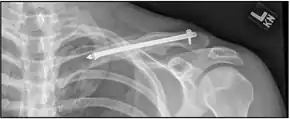

| X-ray of a left clavicle fracture | |

The basic method to check for a clavicle fracture is by an X-ray of the clavicle to determine the fracture type and extent of injury. In former times, X-rays were taken of both clavicle bones for comparison purposes. Due to the curved shape in a tilted plane X-rays are typically oriented with ~15° upwards facing tilt from the front. In more severe cases, a computerized tomography (CT) or magnetic resonance imaging (MRI) scan is taken. However, the standard method of diagnosis through ultrasound imaging performed in the emergency room may be equally accurate in children.[6]

Clavicle fracture